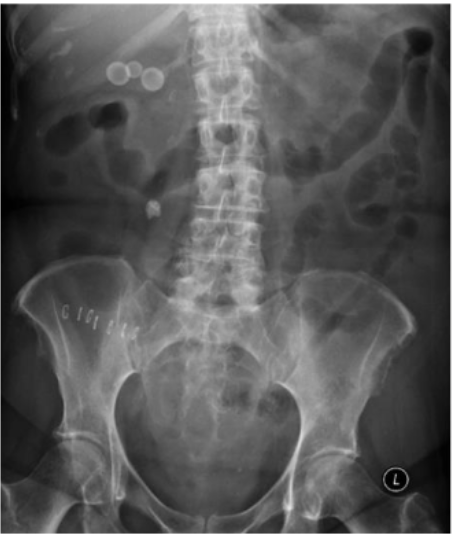

What is this and what type of scan

Calcifications, AXR